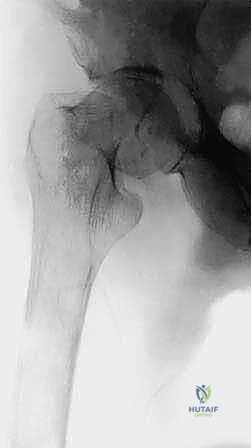

* عظم الفخذ (Femur): أطول وأقوى عظام الجسم، وإصابته تهدد قدرة المريض على المشي.

1. حدوث كسر مرضي فعلي في عظم رئيسي (مثل الفخذ).

1. التثبيت الوقائي الداخلي (Prophylactic Internal Fixation)

إذا أظهرت الأشعة أن العظم ضعيف جداً وعلى وشك الانكسار، يقوم الدكتور هطيف بوضع أسياخ نخاعية معدنية (Intramedullary Nails) أو شرائح ومسامير متطورة داخل العظم لتدعيمه ومنع الكسر قبل حدوثه. هذه الجراحة الاستباقية توفر على المريض آلاماً مبرحة ومضاعفات خطيرة.

| عظم الفخذ (القسم العلوي) | كسر عنق الفخذ، العجز عن المشي. | استبدال مفصل الورك بمفصل صناعي (Arthroplasty). |

| جسم عظم الفخذ أو الساق | كسر مرضي كامل أثناء التحميل. | التثبيت بمسمار نخاعي تشابكي (Intramedullary Nailing). |

- الحالة الأولى: سيدة تبلغ من العمر 55 عاماً، متعافية من سرطان الثدي، عانت من ألم مبرح في الفخذ الأيمن وعجز كامل عن المشي بسبب كسر مرضي وشيك. بعد إجراء الفحوصات، قام الدكتور هطيف بإجراء جراحة تثبيت وقائي باستخدام مسمار نخاعي. في غضون 48 ساعة، استطاعت السيدة المشي بدون ألم، وعادت لممارسة حياتها وسط عائلتها.